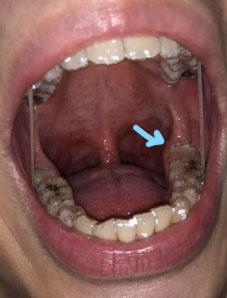

The image shows dark discoloration on the lower back teeth and nearby soft tissue, with the arrow pointing toward the side of the throat and inner cheek area. The lower molars appear heavily stained or decayed, and the surrounding soft tissue looks irritated.

This combination suggests advanced plaque buildup, possible tooth decay, and irritation of nearby oral tissue.